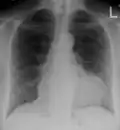

A pericardial effusion as seen on CXR in someone with pericarditis